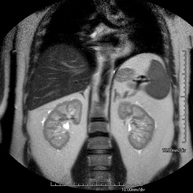

Prova diagnòstica no invasiva que consisteix en l'obtenció d'imatges d'alta definició anatòmica del fetge mitjançant l'ús d'un camp electromagnètic i ones de ràdio (amb un emissor i un receptor). No utilitza radiació ionitzant. Es realitza per estudiar qualsevol lesió localitzada en el fetge. Normalment es requereix l'ús de contrast paramagnètic (Gadolini) per caracteritzar les lesions. És necessari realitzat la prova en dejú (6 hores). - RM de Ronyons

Prova diagnòstica no invasiva que consisteix en l'obtenció d'imatges d'alta definició anatòmica d'ambdós ronyons mitjançant l'ús d'un camp electromagnètic i ones de ràdio (amb un emissor i un receptor). No utilitza radiació ionitzant. Es realitza per estudiar qualsevol lesió localitzada en ambdós ronyons. Normalment es requereix l'ús de contrast paramagnètic (Gadolini) per caracteritzar les lesions. - RM de Glàndules Suprarenals